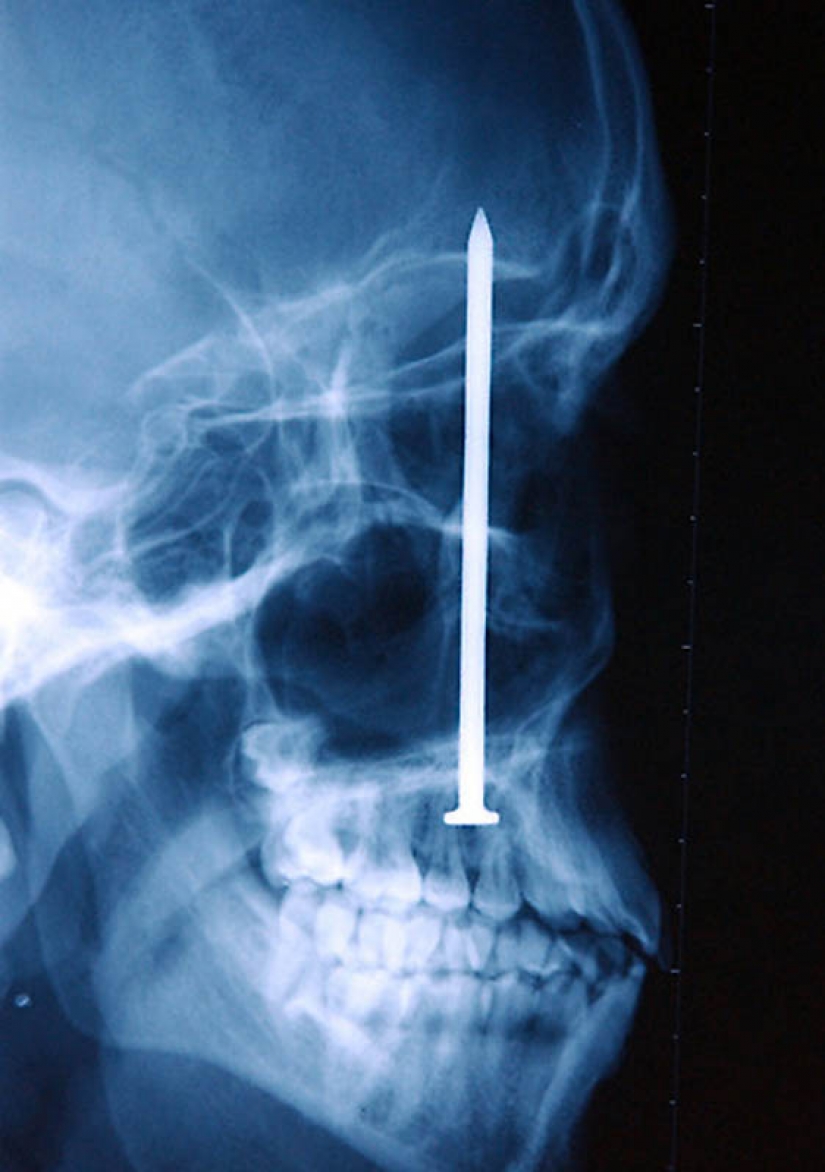

15. Knife in the head 10 year old boy. The boy survived.